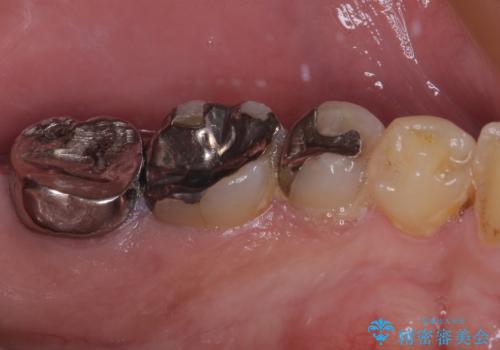

- 食事などで噛んだ時に奥歯が痛むとのことで来院された患者様です。

レントゲン写真より、一番奥の歯の根尖部に大きな病変(炎症により骨が溶けている状態)が認められたため、根管治療を行うこととしました。